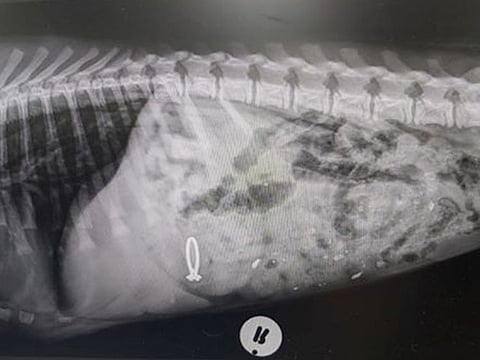

According to Fox News, a dog named Pepper accidentally swallowed his female owner's engagement ring and there is some X-ray imagery at hand as proof of the mischief.

The veterinary hospital then went on to share the X-ray of the ring visible inside Pepper's stomach.